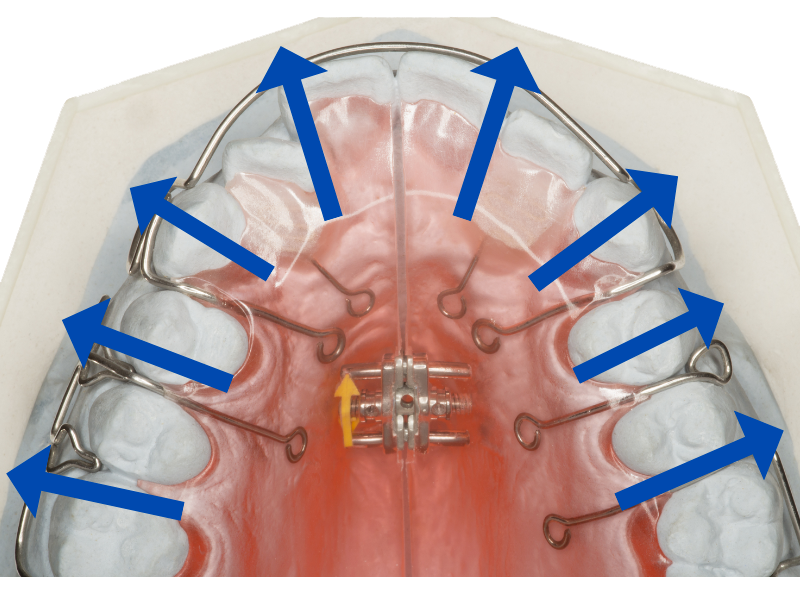

拡大床で、口ゴボになってしまう

スペースが充分に確保できない場合に、前歯しか動かせない格安矯正でよく用いられるのが、拡大床という治療法です。

拡大床

ネジの力を利用して歯を外側へ押し広げることで、前歯を並べるスペースを確保します。

ただ拡大床は、歯列を広げすぎないよう細心の注意を払う必要がある、とても難しい治療法

経験不足の歯科医師では、過度に歯を押し広げてしまい、前歯が口ゴボになってしまうことがあります。

またこの拡大床は奥歯を左右に広げようとしますから、経験不足の歯科医師では、奥歯の位置がおかしくなってしまうことも。

そのため噛み合わせが悪くなって、食事に支障をきたす、という失敗症例もよく耳にします。